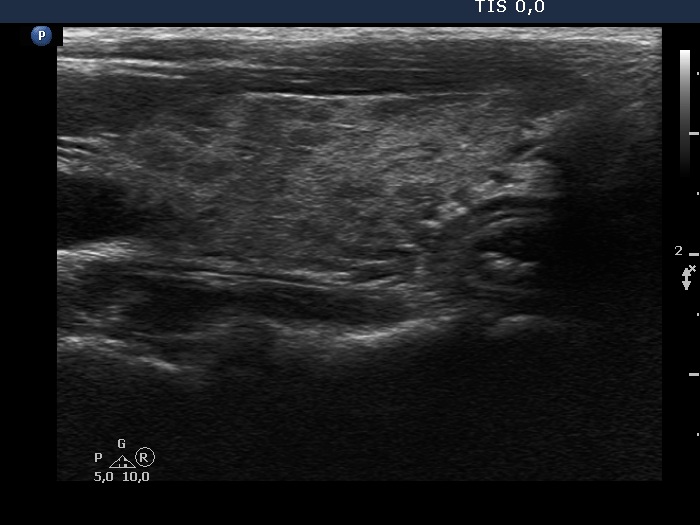

Graves' disease - case 572

Follow-up examination 6 years after the first visit (ultrasonographic picture 5)

Left lobe, longitudinal scan. The pattern is almost identical to that seen at the second examination.